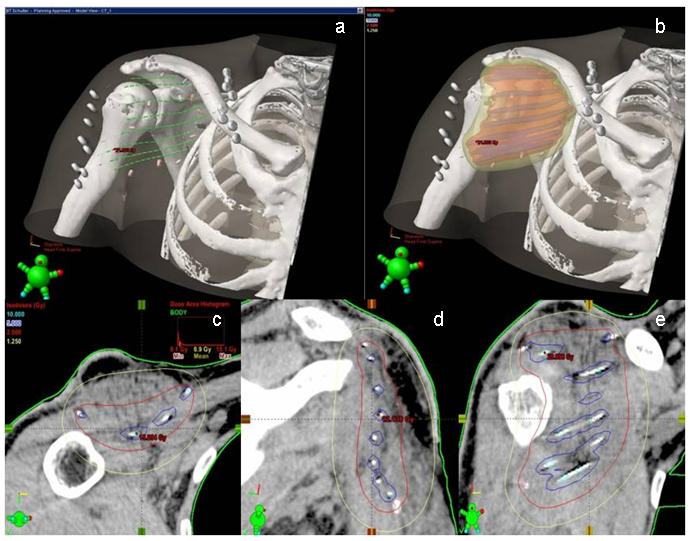

Because of the high risk of local recurrences in solitary surgery and the current tumor size of eight cm, radiation therapy (RT) was recommended in the interdisciplinary tumor board and brachytherapy was initiated with a total of 30 Gy (2x2.5 Gy in 8 days, no radiation on Saturday and Sunday) two weeks after achievement of wound closure. Representative images of dose distribution (Figure 4 [Fig. 4]) show the optimal radiation coverage of the target area.

Interstitial brachytherapy offers minimal normal tissue toxicity due to the steep dose fall-off of the sources and due to the intraoperative applicator placement the target tissue for postoperative radiotherapy can be defined optimally. Regarding total dose values, a National Patterns of Care Study on radiotherapy of desmoid tumors [11] showed an over 80% cure rate in the adjuvant dose range of 36–65 Gy. Radiobiological modelling by the use of the linear-quadratic (LQ) model allows the calculation of the biological equivalent dose (BED) of the used fractionation schedule [13] and results in a total BED of 46.5 Gy on the reference isodose. However, tissue volumes near to the applicators will be irradiated with higher dose (for example the volume covered by the 200% isodose line with BED 93.0 Gy). The quality of the implant can be described by the dose non-homogeneity ratio (DNR), which is the value of the 150% isodose volume divided by the covered volume of the 100% isodose line. In this case it was 0.39 – indicating a homogenous brachytherapy dose distribution.